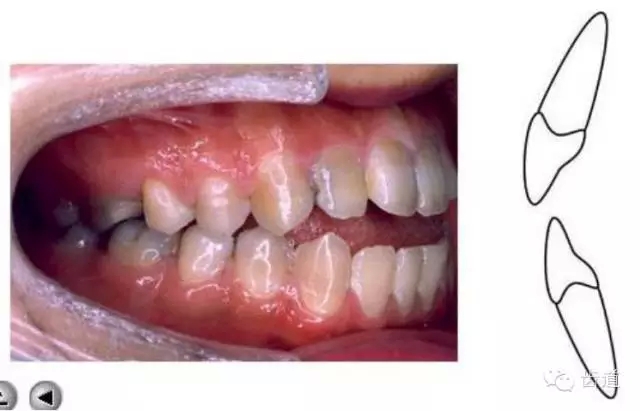

上下牙列間存在著覆蓋、覆牙合

覆蓋Overjet (the horizontal overlap)

覆牙合Overbite (the vertical overlap)

覆蓋(over jet,即超牙合):水平距離

覆牙合(over bite):垂直距離

覆牙合、覆蓋生理意義

a.保護唇頰舌軟組織

b.提高咀嚼效率